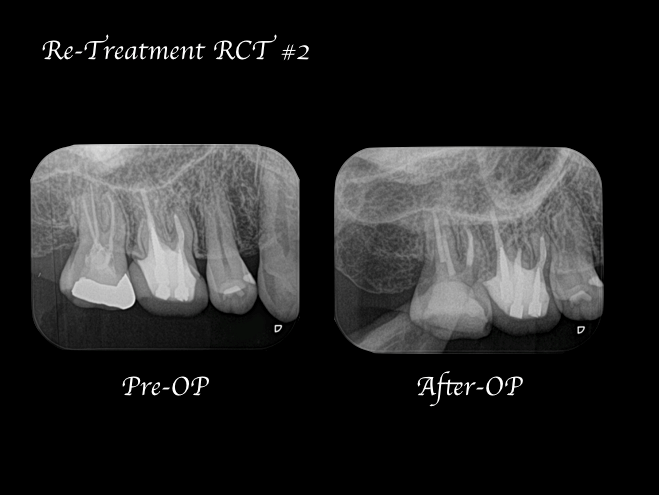

【症例】再根管治療| CT、マイクロスコープを使った精密根管治療